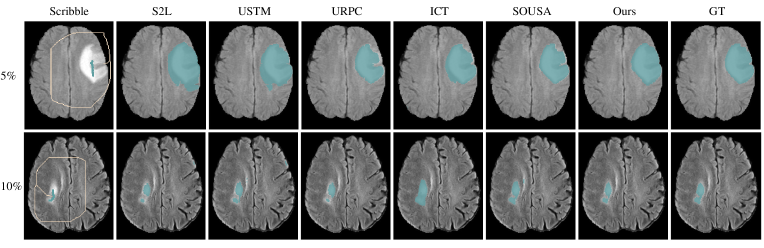

Refer to caption

Figure 3: Visual comparison of weakly semi-supervised segmentation results for the ACDC datasets under different labeled ratios.

ACDC dataset From Table I, all methods demonstrate improvements over the lower bound using only sparse annotations, confirming that learning from unlabeled data can yield model gains. SOUSA method outperforms other WSSS methods adopted from weakly supervised methods (S2L, USTM) and semi-supervised methods (URPC, ICT) and achieves suboptimal results. Our method achieves the best performance in Dice, JI, 95HD, and ASD compared to other methods, with 0.7937 and 0.8186 Dice scores on 10% and 20% labeled ratios respectively. Our method fully leverages the scribble annotations and unlabeled data, achieving superior Dice scores over the upper bound utilizing dense annotations by 0.1113 and 0.0607 on two label ratios respectively. Higher improvement above the upper bound and other comparative methods with lower label ratios show our method can resist noise better. The visual comparison results are shown in Figures 3, in which our method gets the optimal segmentation with more accurate boundaries.

BraTS2019 dataset Segmenting whole brain tumors is a more challenging task due to the inherent ambiguity and diverse shapes of tumors. As shown in Table II, all methods show improvements over the lower bound, but none of them reported better results than the upper bound (0.7848/5% labeled ratio and 0.8093/10% labeled ratio). The results indicate that it is challenging to segment the whole tumors with scribble annotations, especially at a 5% labeled ratio with a gap of 0.0342 Dice score from the upper bound. However, our approach reaches a competitive result (0.8064 Dice and 15.47 95HD) with the upper bound when using a 10% labeled ratio through superpixel propagation. The visualization of the comparison results is given in Figure 4. Our method can better delineate the tumors than other WSSS methods.